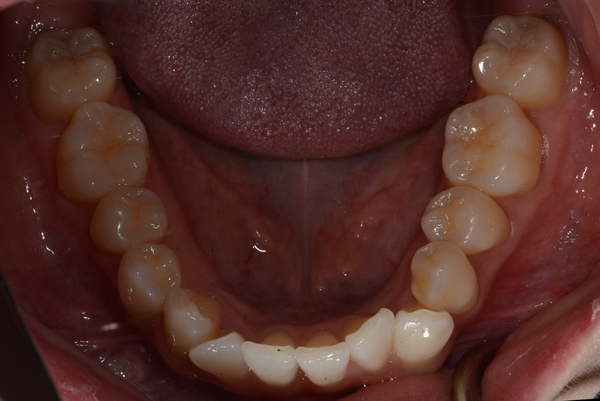

ガタガタとした歯並びや八重歯(叢生)CASE69